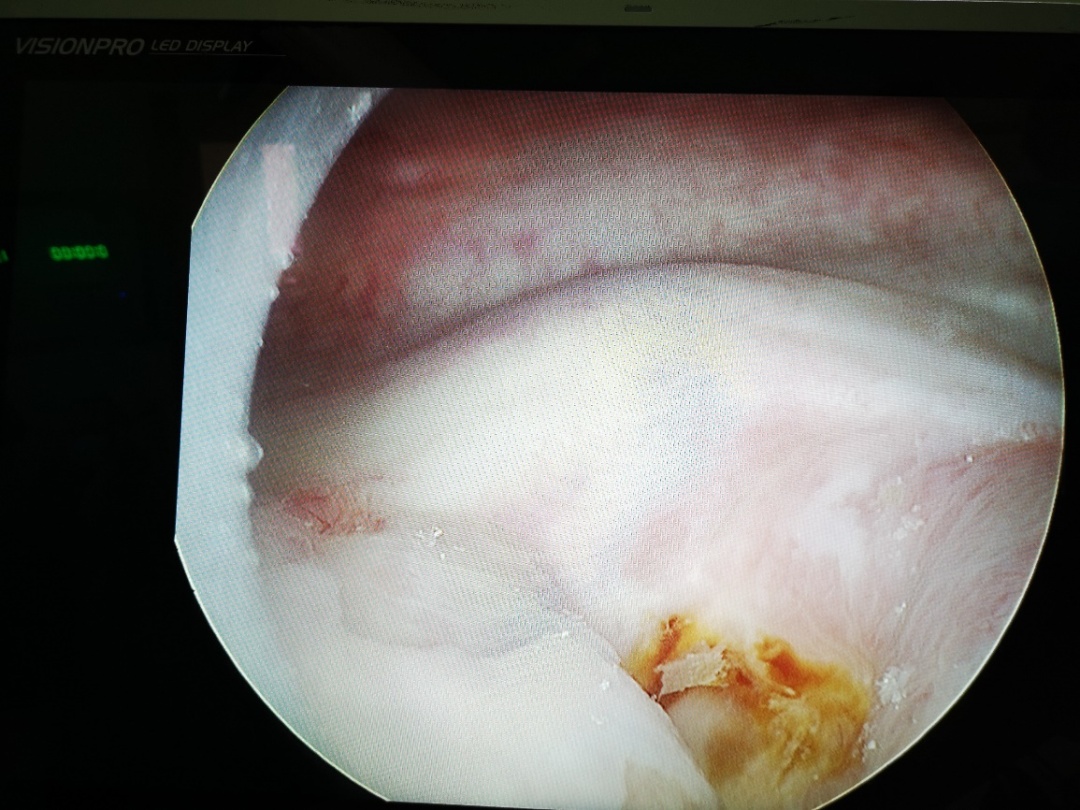

▲膀胱镜检查瘘口